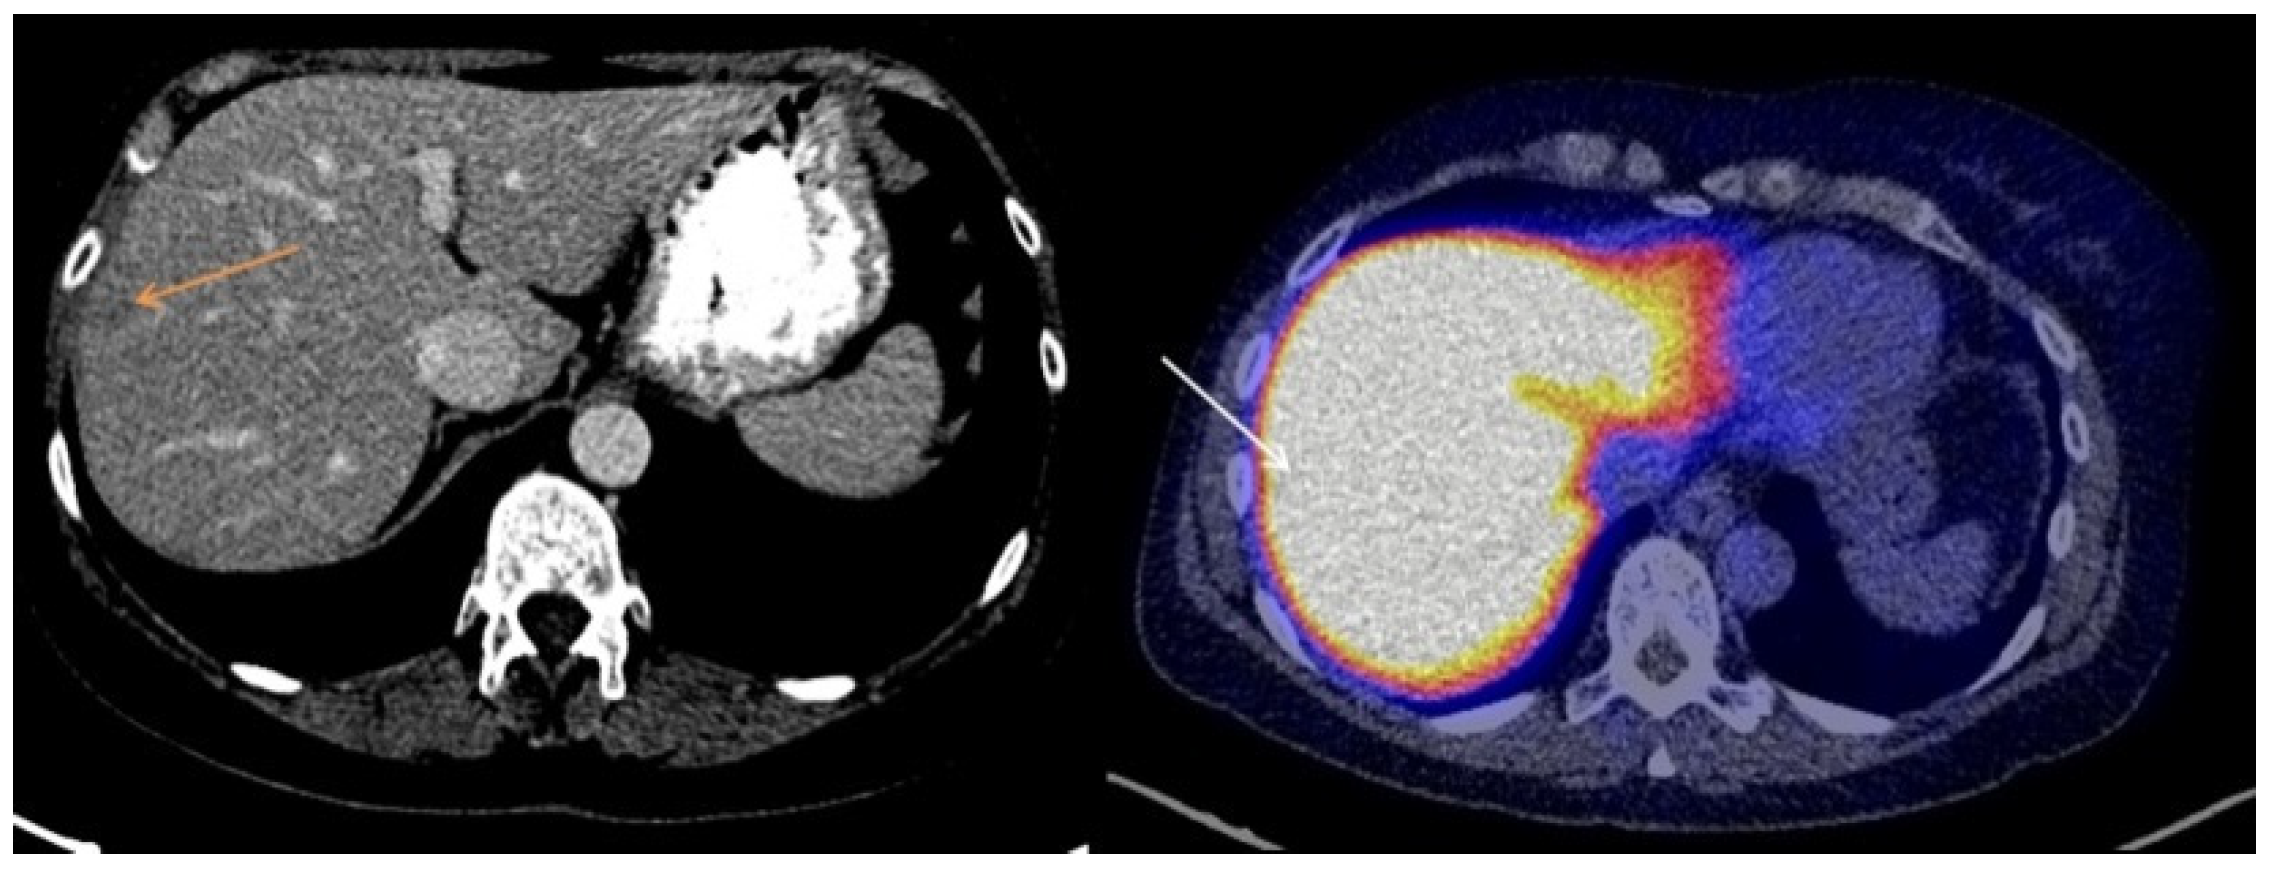

3.2. Visual Assessment of [18F]-FES Uptake

3.3. Quantitative Evaluation of [18F]-FES Uptake